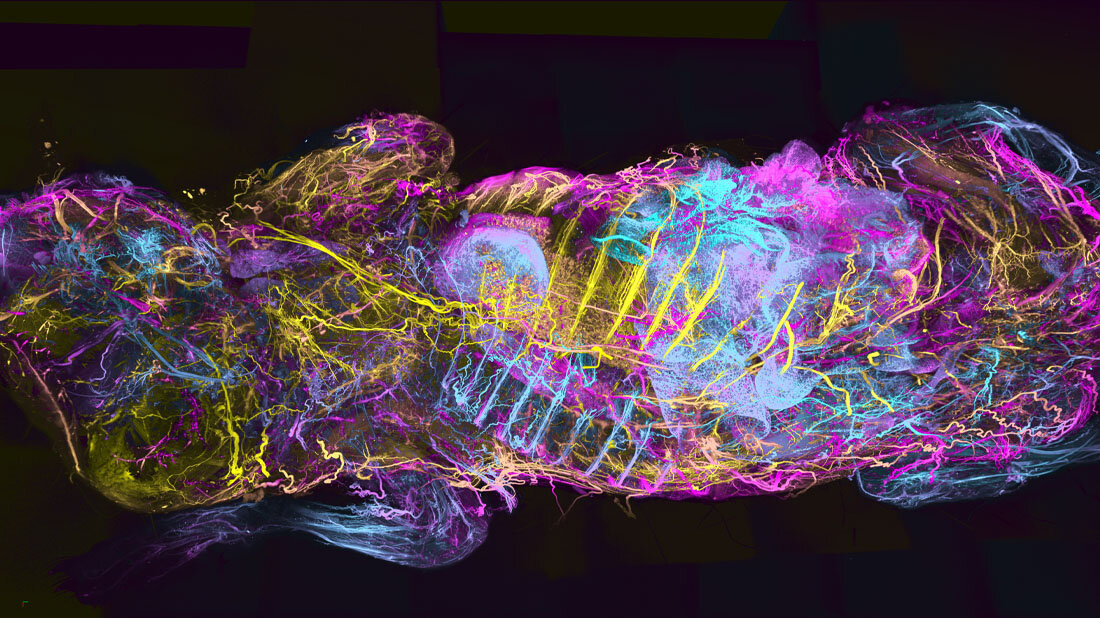

Im Detail umfasst der Versuchsablauf von WildDISCO die Verteilung von Antikörpern gekoppelt mit fluoreszierenden Markern im gesamten Körper des toten Tieres über das Blutgefäßsystem. Im nächsten Schritt werden die Tiere optisch transparent gemacht, indem sie mit bestimmen Chemikalien behandelt werden, um das Gewebe durchlässiger für Lichteinstrahlung zu machen. Daraufhin wird ein Lichtscheibenfluoreszenzmikroskop für die Untersuchung eingesetzt, wobei die Wissenschaftlerinnen und Wissenschaftler ein Fluoreszenzsignal detektieren, bei dem ein spezifischer Antikörper an die Struktur, das Molekül oder die Zelle von Interesse bindet. Fortgeschrittene computergestützte Werkzeuge erstellen dann körperweite Karten über die Lokalisation der Moleküle, die von Interesse sind.

Mit WildDISCO waren die Forscherinnen und Forscher in der Lage, detaillierte Karten der zellulären Strukturen und schließlich Ganzkörper-Atlanten von Mäusen zu erstellen mit Fokus auf dem Nervensystem, den lymphatischen Gefäßen, den Blutgefäßen und den Immunzellen. Mit dieser Methode entdeckten sie bereits, dass das Darmmikrobiom eine bedeutende Rolle bei der Entwicklung des enterischen Nervensystems, dem Netzwerk an Nerven entlang des Magen-Darm-Trakts, spielt. Außerdem wurden Tumor-assoziierte lymphoide Strukturen (TLS) im Zusammenhang mit der Ausbreitung von Brustkrebs kartiert, was wiederum Einblicke in die Auswirkungen dieser Strukturen auf die Immunantwort auf Tumore liefert.